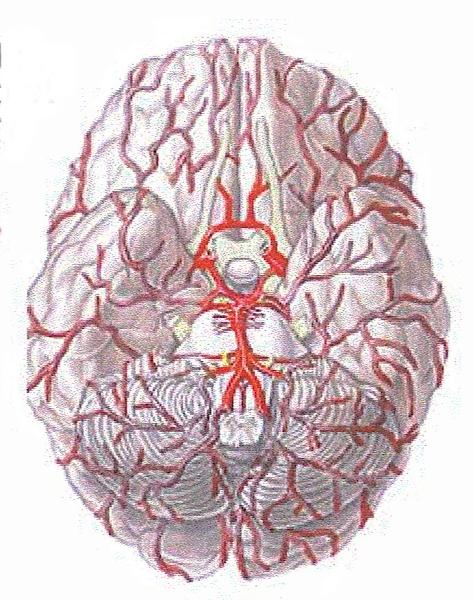

Basilar artery

Circle of Willis

Internal/external/common carotid artery

internal/external/common jugular vein

Vertebral artery